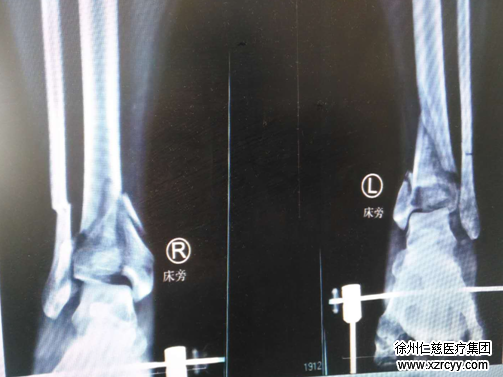

袁医生让刘大强先办理住院手续,当晚,就给他做了双跟骨牵引。牵引两周后,刘大强小腿远端消肿明显。

术中,手术团队聚精会神,分工协作,先进行右踝关节骨折的复位及内固定。在右外踝侧做10厘米长切口,见关节粉碎严重,予以手法复位腓骨远端骨折端,六孔钢板固定;小腿远折端粉碎严重,关节面消失,复位骨折块,克氏针固定,手法复位关节面,克氏针固定,L型锁定钢板固定;右踝后内侧切6厘米长切口,手法复位粉碎骨折端,克氏针固定,钢板固定。同样的方法,在左踝关节的前侧、内侧分别手法复位骨折端,克氏针固定,L型钢板固定。